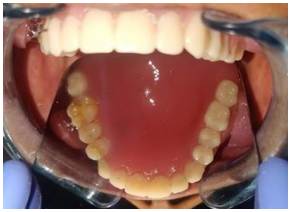

Primary impressions of maxillary and mandibular arches were made using impression material (Y Dents, MDM Corporation, Delhi). Custom trays were made using autopolymerizing acrylic resin. Border molding was done using low fusing impression compound (DPI Pinnacle, The Bombay Burmah Trading Corporation Limited, Mumbai, India) and wash impression was made with medium body addition silicone impression material (Aquasil, Dentsply). Jaw relations were recorded. For the try-in appointment waxed denture was first tried for occlusion and esthetics. At the same appointment, cheek plumpers were made in wax and were attached to the upper waxed-up denture. Then it was evaluated to give the patient a fuller appearance. A dramatic change in the appearance with and without wax-up cheek plumper was observed and it was immediately accepted by the patient. The waxed plumper was separated from the waxed-up denture. After that flasking and dewaxing procedures were completed separately for the final prosthesis and cheek plumpers. The mold space was packed with heat-polymerizing acrylic material (DPI, Mumbai, India) and curing procedures were performed according to the manufacturer’s instructions. After deflasking, the cured final prosthesis and plumpers were retrieved. Trimming, finishing, and polishing procedures were performed. Then a pair of commercially available magnets (cobaltsamarium, Ambika Corporation, New Delhi, India), 5 mm in diameter and 2 mm in thickness was employed to retain the cheek plumper with final prosthesis. Provision for placement of magnets in the flange of the final prosthesis and in the cheek plumper was made and positioned with the help of autopolymerizing resin. Complete polymerization was ensured by placing in a pressure pot and finishing and polishing was then carried out. The attachment of plumper to the prosthesis was first checked outside the patient’s mouth. The prosthesis along with the plumper was then checked in the patient’s mouth. for comfort, function and esthetics . The patient was educated about the positioning of the plumper to the prosthesis. The patient’s demands were fulfilled.  She was called form follow up to evaluate any soreness or looseness of dentures.

The magnet retained cheek plumper prosthesis is a simple and non invasive treatment option. It  successfully restores cheek contour, improves the facial esthetics and psychological well being of the patient. Magnetic retention for sunken cheek patients is advantageous due to its compact size and strong attractive forces; however, over a period of time the magnets used intraorally require replacement due to lack of long-term durability in oral conditions.